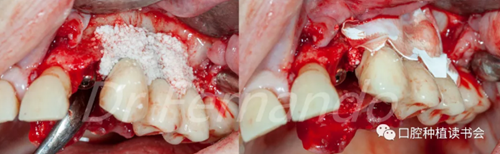

然后根據(jù)種植體周圍炎的標準治療程序,先使用磷酸&氯己定凝膠處理種植體表面2分鐘后,接著使用抗生素溶液(透明質(zhì)酸鈉哌拉西林他唑巴坦)處理5分鐘,然后使用Cerasorb ?M 骨粉植骨(Curasan?-科盧森)(圖 21)。

圖21 機械&化學(xué)凈化種植體表面后,使用Cerasorb ?M 骨粉植骨

在骨粉上方覆蓋 Osgide? 可吸收膠原膜(Curasan?-科盧森) ,用絲線嚴密關(guān)閉傷口(圖 22 )

圖22 植骨區(qū)覆蓋可吸收膠原膜,關(guān)閉創(chuàng)口